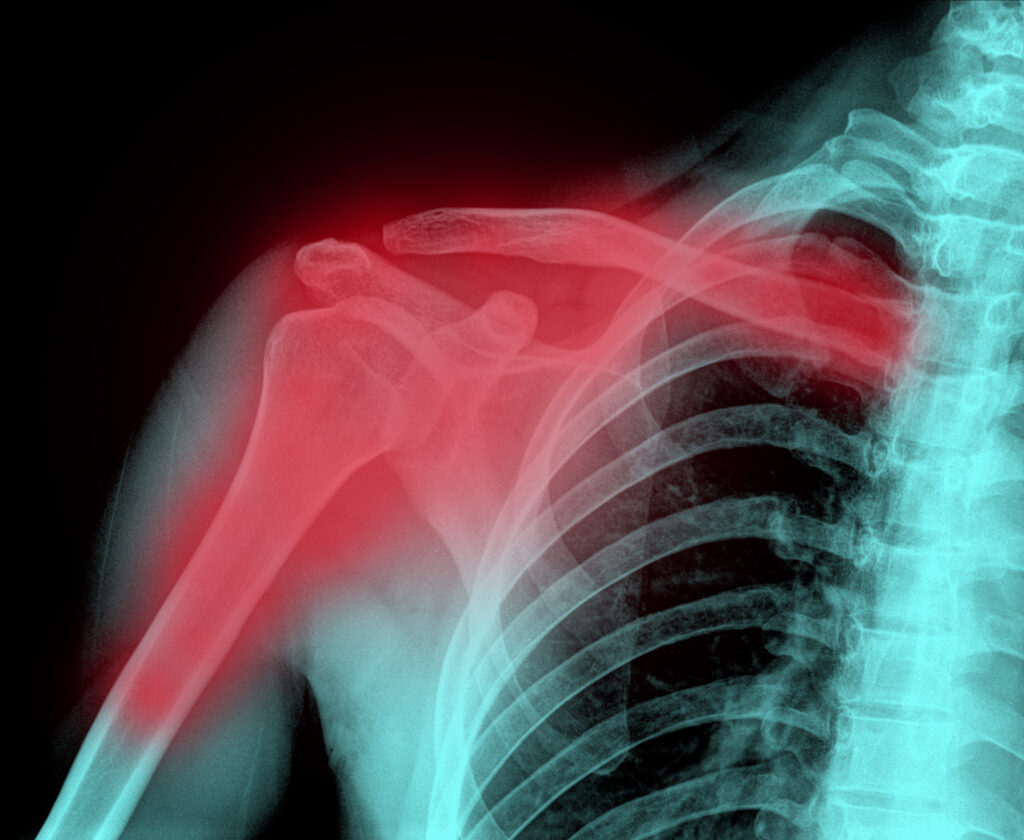

Diagnosis is the first step toward proper treatment. Your doctor will generally begin with a physical examination, checking your shoulder, arm, and hand for tenderness, swelling, bruising, and any signs of nerve or blood vessel damage.

Imaging studies may be used to confirm the fracture. X-rays are typically taken from several angles to clearly show the injury and determine the fracture type. If the break is complex, especially near the joint or if the bone is severely displaced, a CT scan may be ordered for a more detailed, three-dimensional view. This can be especially helpful when planning surgery.